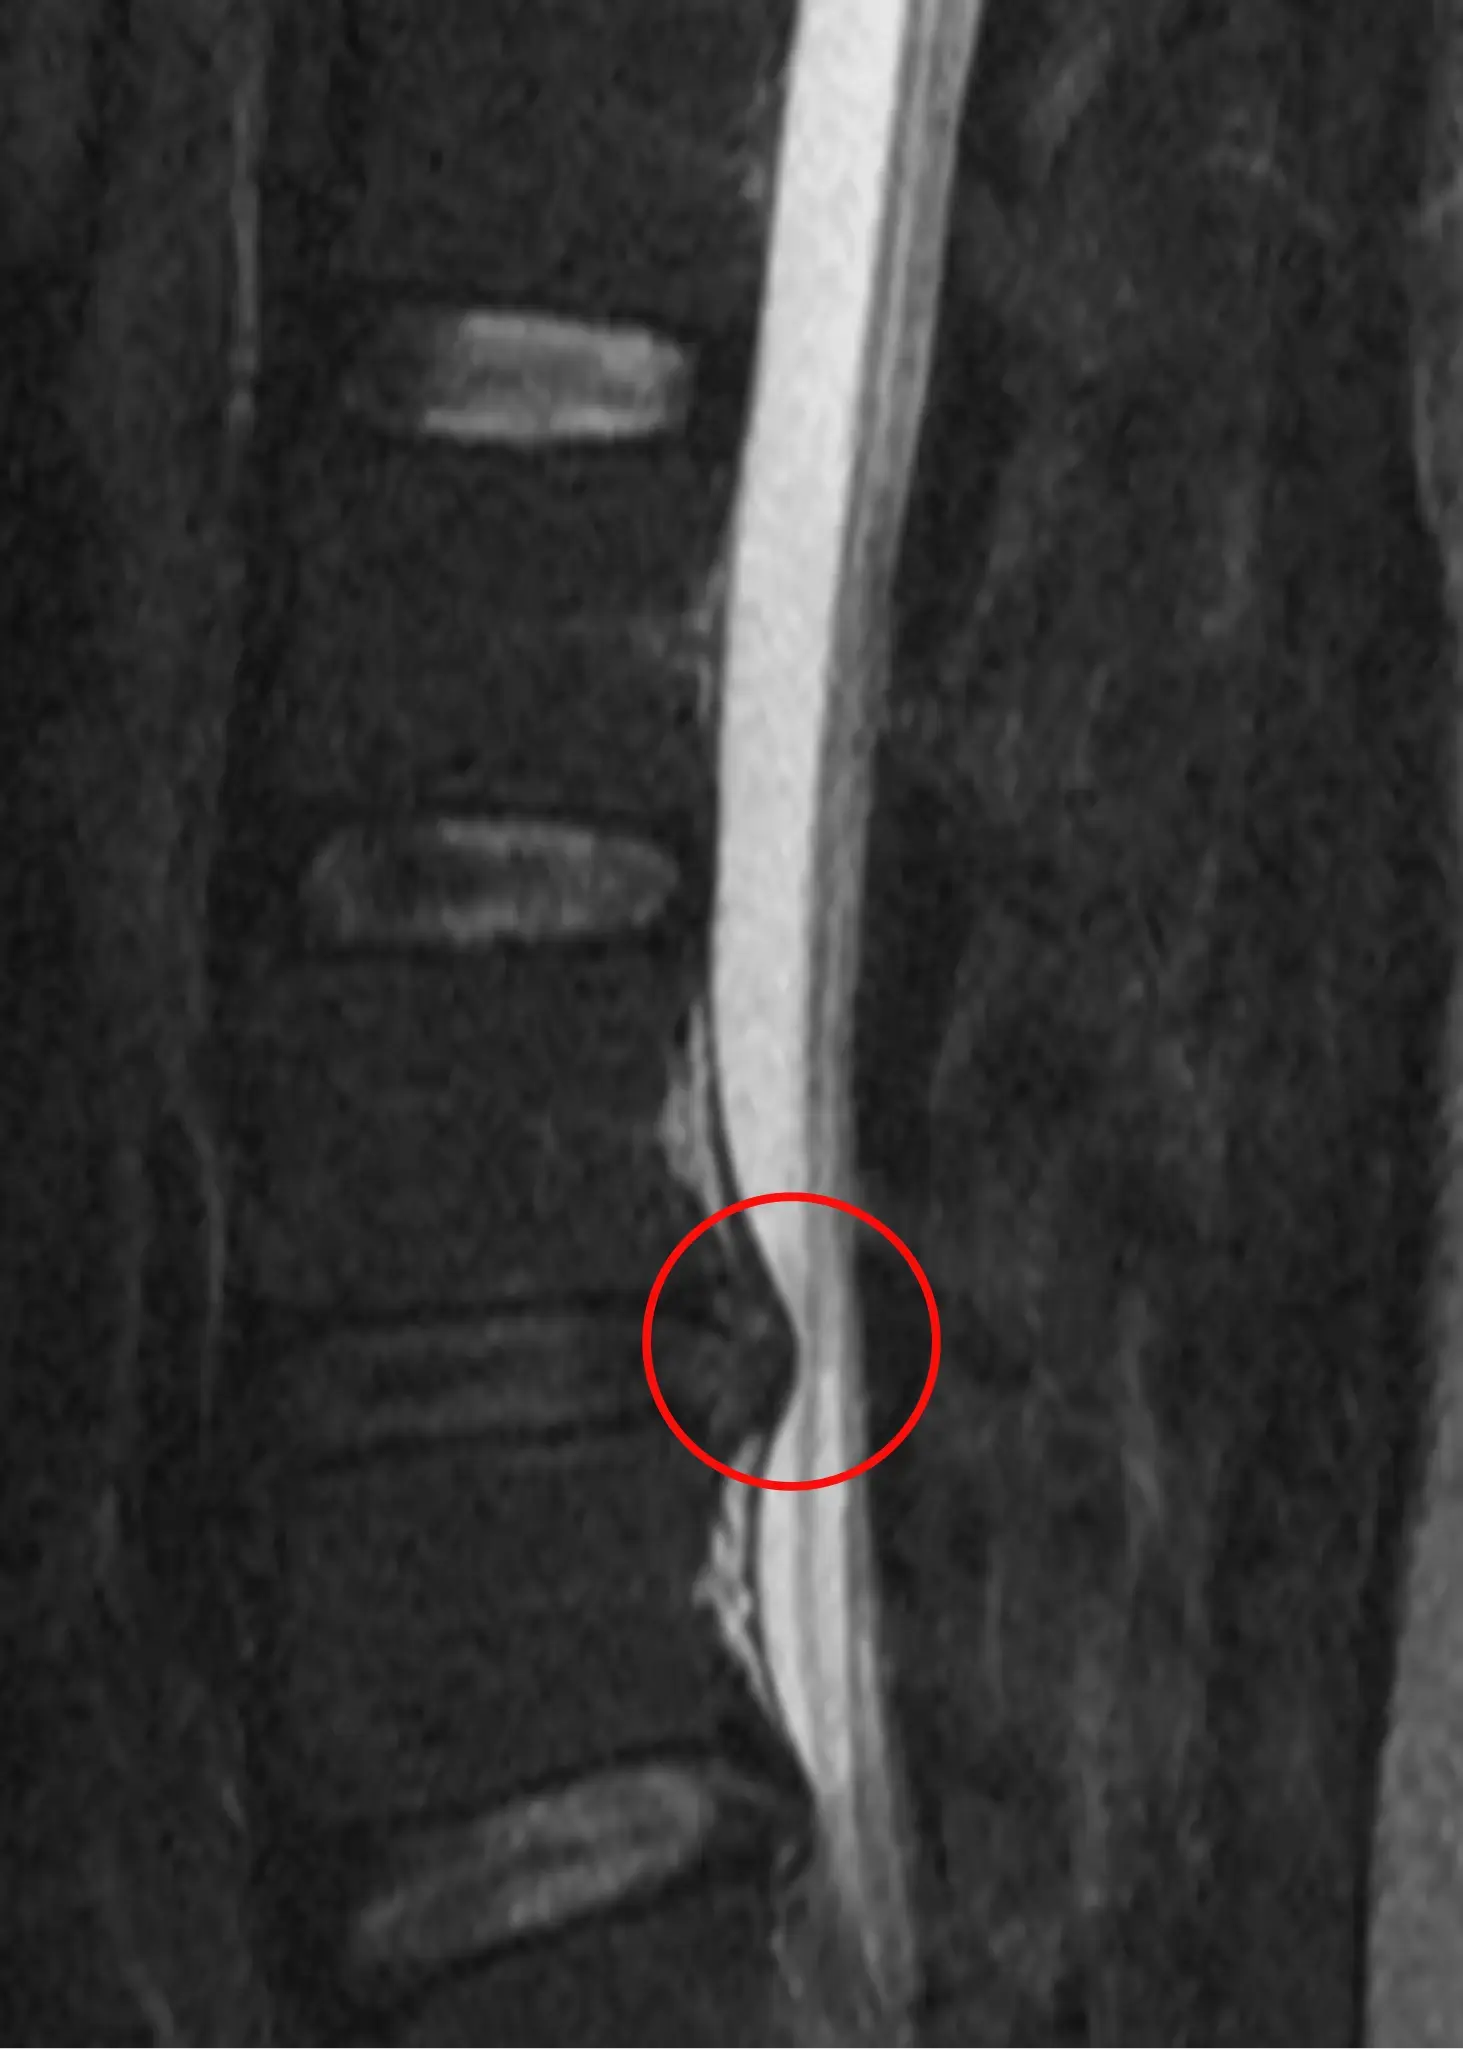

Between each vertebra in your spine are intervertebral discs—shock-absorbing structures made of a tough outer layer (annulus fibrosus) and a soft inner gel (nucleus pulposus). A lumbar disc herniation happens when the inner material pushes out through a tear or weakened spot in the outer layer, often pressing on nearby nerves.

Most herniations happen in the lumbar spine—the lower back—because this region carries most of your body’s weight and is heavily involved in bending, lifting, and twisting. When a disc herniates and compresses a spinal nerve root, symptoms can extend far beyond the spine, often down into the buttock, thigh, or lower leg.

A clinical exam can often identify the likelihood of a disc herniation. In many cases, a detailed history and physical exam are enough to begin conservative care. However, if symptoms persist or worsen despite treatment, or if neurological signs like foot drop are present, an MRI may be ordered to confirm the diagnosis and rule out other conditions.